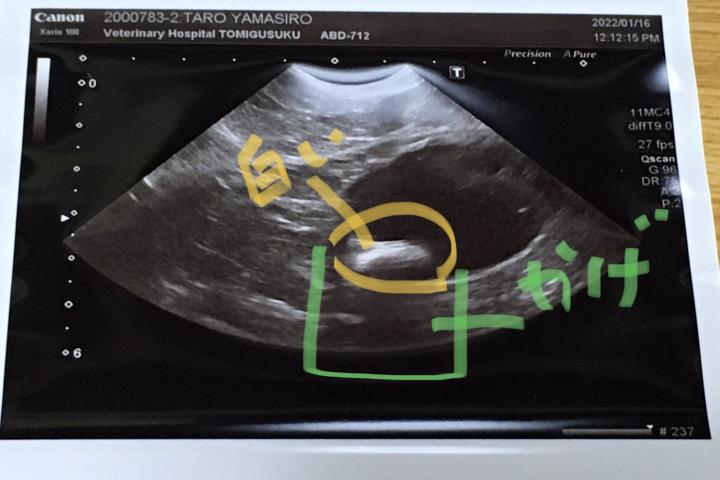

先生が、エコーに反応した。

真ん中の写真に反応。

写真私がマーカーいれましたが、白いのは明らかに結石だろうと。

言われてないか?というけど、全く覚えなし。

固形物にエコーが当たると、その下にまでエコーが届かないから

白いものの下は暗くなっている。と説明されました。